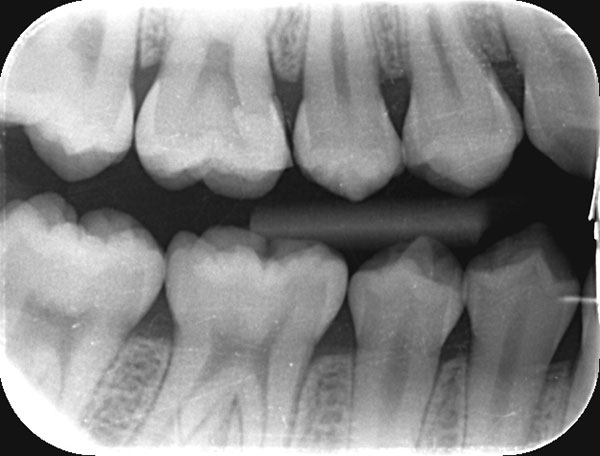

術前

術後

症例について

主訴:

歯茎が腫れたので診てほしい

治療内容:

感染や炎症を起こした歯の神経を取り除き、根の中を清掃・消毒したうえで再感染を防ぐ治療です。

治療期間:60分 1回

費用:初回根管治療 132,000円(税込)/ 支台築造 16,500円(税込)

治療に関わるリスクまたは副作用:

症状が改善しない場合や、再治療、外科的歯内療法が必要になることがあります。